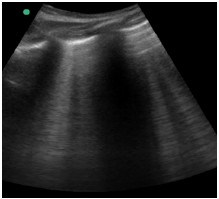

Um paciente de 40 anos de idade, vítima de queda de 9 metros (estava trabalhando quando o telhado cedeu), trazido à sala vermelha pelo SAMU, foi admitido com PA = 80 mmHg x 40 mmHg, FC = 120 bpm e tempo de enchimento capilar = 4 segundos. O emergencista procedeu ao e-fast, que evidenciou o achado apresentado na imagem.

Hemitórax direito superior